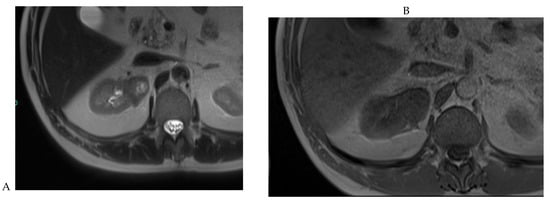

Figure 7.

Papillary renal cell carcinoma in the right kidney of a 75-year-old-woman. (A) Axial T2-weighted fast SE image shows a homogeneous 1.8 cm mass in the posterolateral region of the right kidney, with a lower SI compared to renal parenchyma. Transverse in-phase (B,C) opposed-phase MR images do not show a significant signal loss on the opposed-phase image. (D) The ADC map shows restriction of tumor diffusion into the renal mass. Transverse nonenhanced (E) and gadolinium-enhanced T1-weighted gradient-echo spoiled MR images in (F) corticomedullary, (G) nephrographic, (H) and delayed phase images show progressive enhancement without washout; the mass is hypovascular compared to the renal cortex.